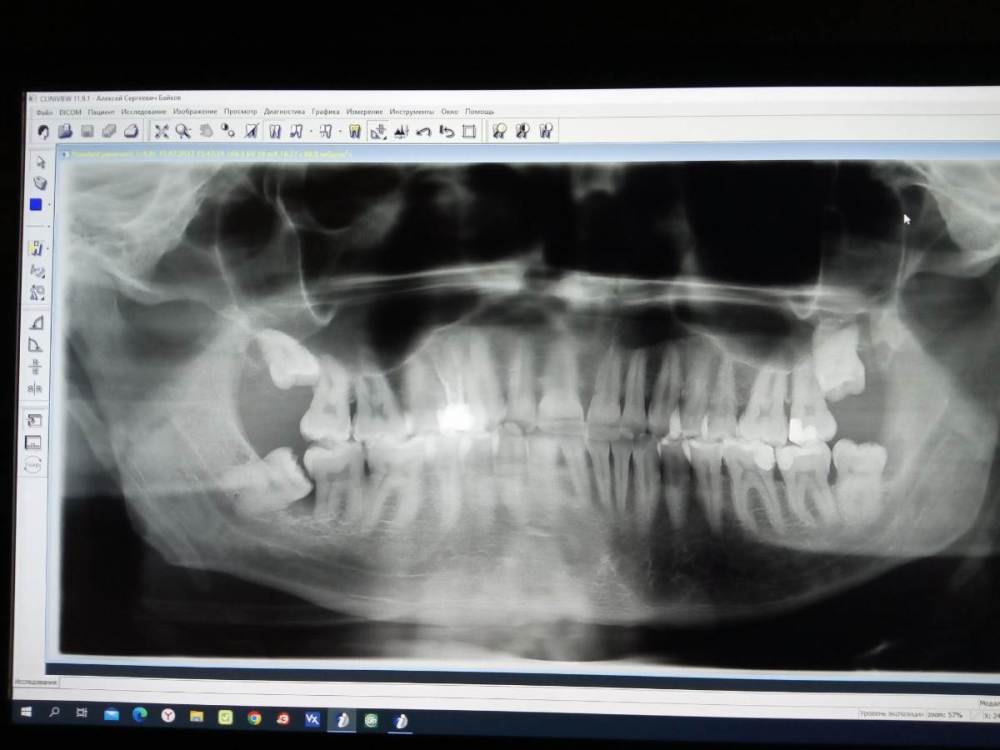

Bruz Опубликовано 22 ноября, 2022 Автор Поделиться Опубликовано 22 ноября, 2022 (изменено) Снимок Изменено 22 ноября, 2022 пользователем Bruz Ссылка на комментарий

Bruz Опубликовано 22 ноября, 2022 Автор Поделиться Опубликовано 22 ноября, 2022 (изменено) Посмотрите пожалуйста снимок. Он за август до удаления правой нижней 8-ки (на снимке она слева, под наклоном шла). Прошло три месяца. Сейчас в ноябре началось побаливание где-то справа и отдает немного в висок, то поболит, то проходит, и в чем причина не могу понять, есть несколько версий. 1. На снимке между этой наклоненной 8-кой и 7-кой потемнение у корней, врач удалявший эту 8-ку прсмотрев это затемнение сказал, что это воспаление. Возможно ли, что после удаления зуба это воспаление не прошло и теперь у этой 7-ки кариес корня? После удаления 8-ки к задней стенке этой 7-ки не подлезть, там десна наросла и врач туда не сможет с зеркалом добраться чтобы посмотреть состояние зуба сзади. Кое-как чищу там щеткой, если попробовать почистить ниткой заднюю стенку этой 7-ки, то на уровне десны нитка за что-то задевает и вверх не идет, может ли это быть от кариеса или может врач пока удалял эту 8-ку соучайно подпилил 7-ку и теперь нитка за спил задевает? 2. На правой верхней 7-ке (на снимке она тоже слева) на момент снимка был кариес рядом с 6-кой, видно ли на снимке состояние этой 7-ки, есть ли пульпит? Эти 7-ки обе и нижняя и верхня чувствительны на холодную воду. При постукивании ложкой не болят. 3. Насчет верхних 8-рок врач сказал, что не стал бы их трогать, что они стремные и выходят в какую-то полость или пазуху и могут быть проблемы с удалением или после. Кстати, языком они не прощупываются, там десна после обоих 7-рок, значит 8-ки не прорезаны еще? Мне кажется, что боль может еще давать правая верхняя 8-ка (на снимке слева), которая пошла в рост и давит на 7-ку. Может тогда эту 7-ку удалить, раз на ней кариес и возможно ее толкает 8-ка, отсюда и побаливает где-то там? Пусть тогда 8-ка прорастает на ее место? 4. Подскажите, почему на снимке справа снизу большая темная область, это снимок плохо получился или там проблема с челюстью? Снимок вообще нормальный или лучше в другой клинике в следующий раз делать? Изменено 22 ноября, 2022 пользователем Bruz Ссылка на комментарий

IvanK Опубликовано 23 ноября, 2022 Поделиться Опубликовано 23 ноября, 2022 Гадать по старому снимку я не умею) Для диагностики Ваших болей нужны хорошие прицельные снимки зубов этой половины или (что лучше) свежая компьютерная томография Точно могу сказать, что 3.8 (нижняя левая 8ка) точно имеет показания к удалению Ссылка на комментарий